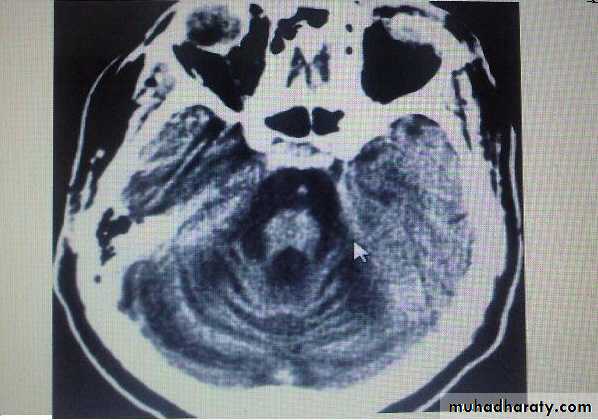

Group of heterogeneous inherited disorders characterized by slowly progressive cerebellar ataxia that affects gait early and severely and may eventually confine the patient to bed. They show considerable clinical variability .Most of them begin in adulthood. Atrophy of the cerebellum and sometimes also of the brainstem may be apparent on CT or MRI scans. Definitive diagnosis is by genetic testing. Treatment is symptomatic.Fridrich Ataxia

Investigation:1- MRI brain and spine.

develop in chronic alcoholics lasting 10 or more years, probably as a result of associated nutritional deficiency. most common in men. usually start between 40 and 60 years.Degenerative changes are largely restricted to the superior vermis, usually insidious in onset & gradually progressive over weeks to months eventually reaching a stable level of deficit, Gait ataxia is a universal feature, heel-knee-shin test is +ve in about 80%. CT scan or MRI may show cerebellar atrophy. No specific treatment is available. Abstinence from alcohol, combined with adequate nutrition, leads to stabilization in most cases. All patients with this diagnosis should receive thiamine to prevent development of Wernicke encephalopathy.